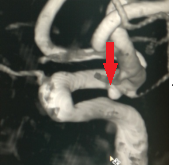

术后复查CTA

图片2.png